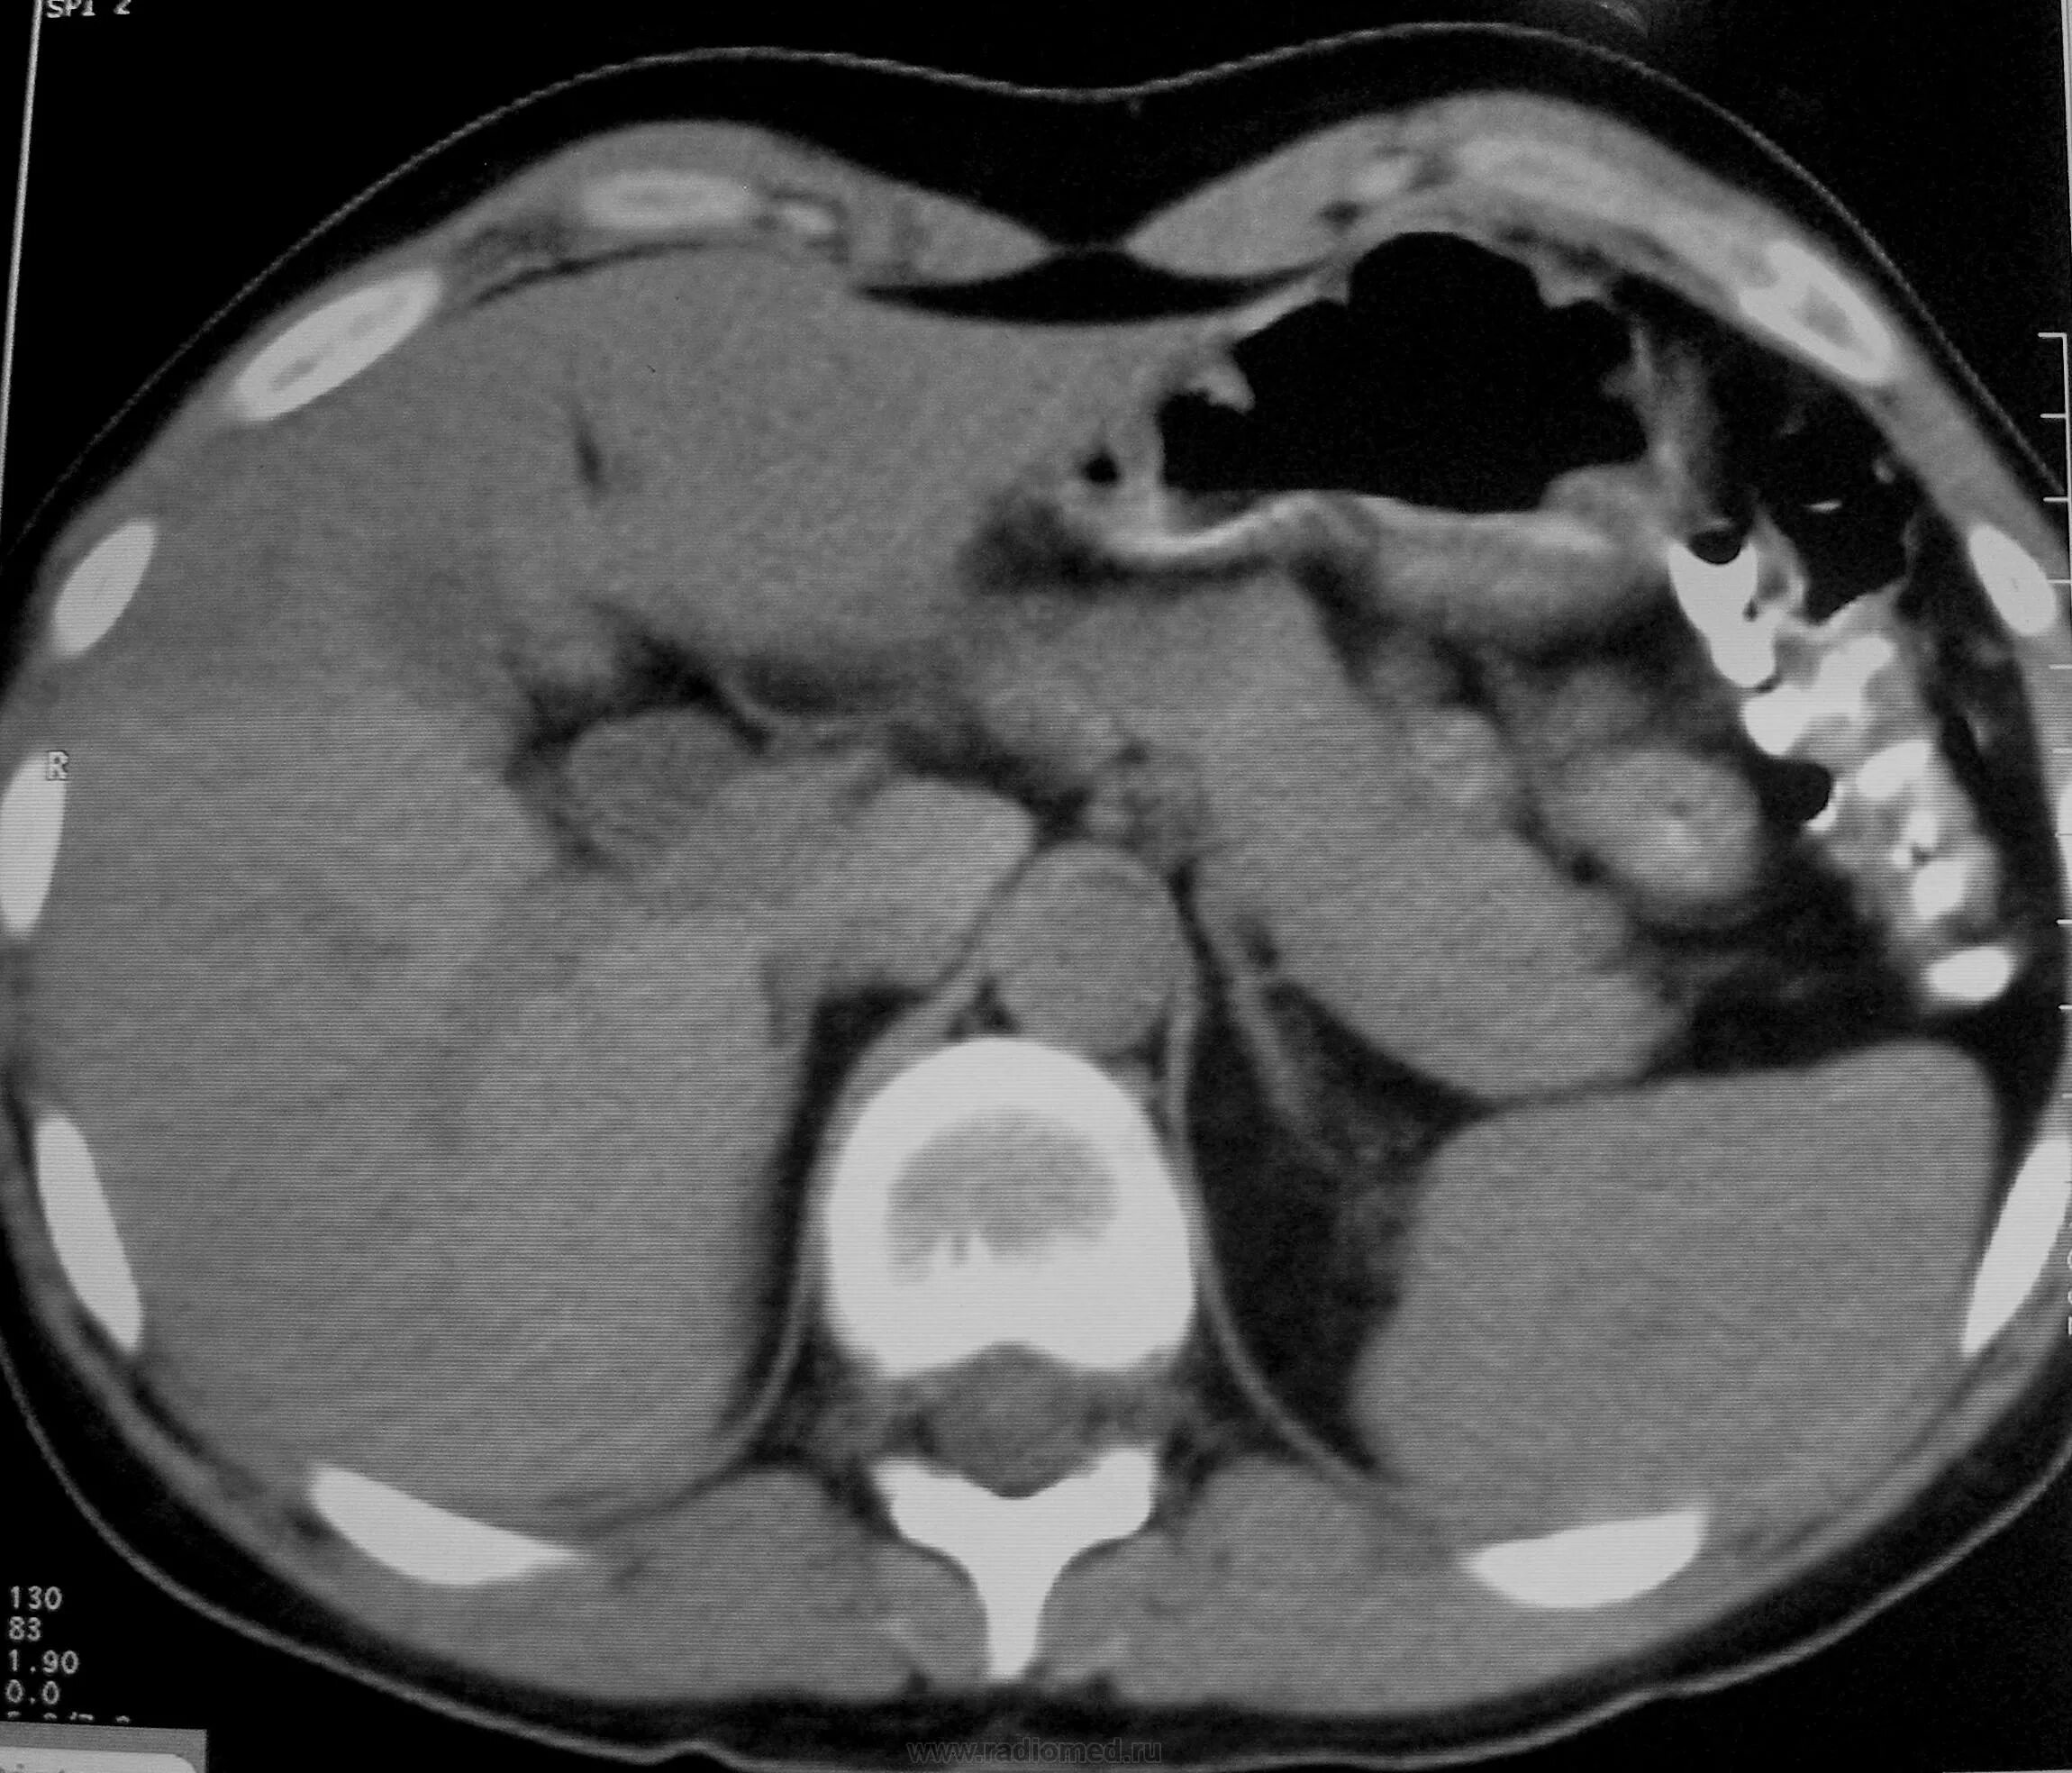

Мрт кисты поджелудочной